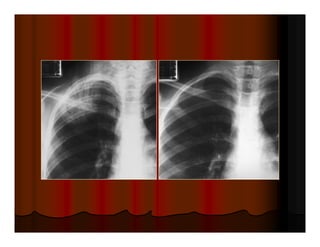

Được xem là hít đủ sâu khi ta thấy được hình chiếu của xương

sườn lên phổi 6 cung sườn trước hoặc 10 cung sườn sau.

Hít không đủ sâu Hít đủ sâu